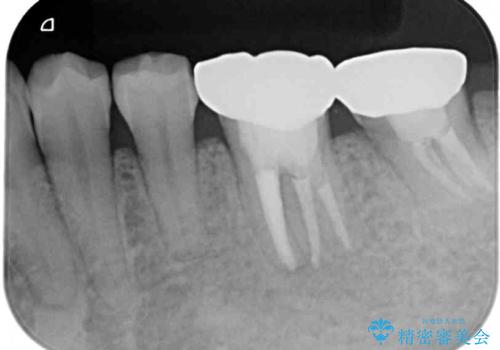

矯正治療後には、左下奥歯の症状がないことを確認し、セラミッククラウンにて補綴治療を行うこととしました。

矯正治療後のレントゲン写真では、根尖部に認められた病変(骨の溶けていた像)は消失していることが分かりました。